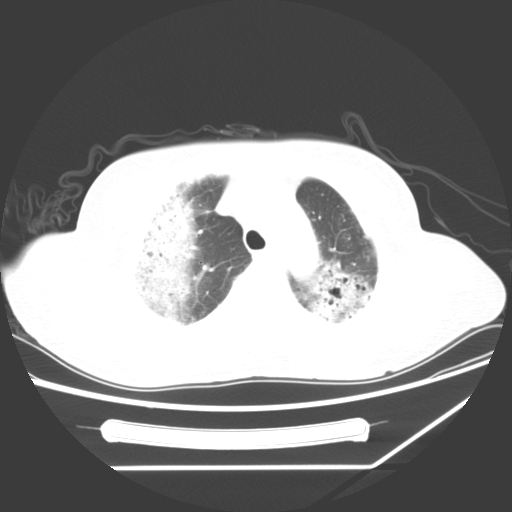

标题: CT25393:病人45岁,咳嗽,吐黄痰带血丝,发热,胸闷月余

1、左肺中央型肺癌并双肺弥漫性转移   2、双肺部感染    3、肺大泡     4、左侧胸腔积液

双侧肺弥漫性病变,可见“空泡征”及“蜂窝征”,考虑肺泡癌可能性大,左侧胸腔积液,考虑胸膜受累可能!

1)不排除肺泡癌可能。2)左侧胸腔积液。